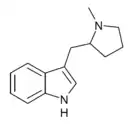

| Pyr-T | artificial | H | (CH2)4 | 3-[2-(Pyrrolidin-1-yl)ethyl]-1H-indole | 14008-96-9 | |

MPMI[26] | 3-[(1-methylpyrrolidin-2-yl)methyl]-1H-indole | 143321-54-4 |